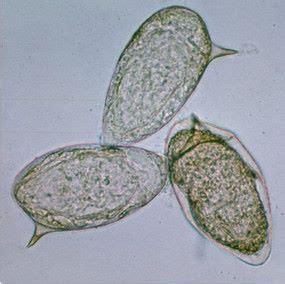

Shistosoma mansoni eggs